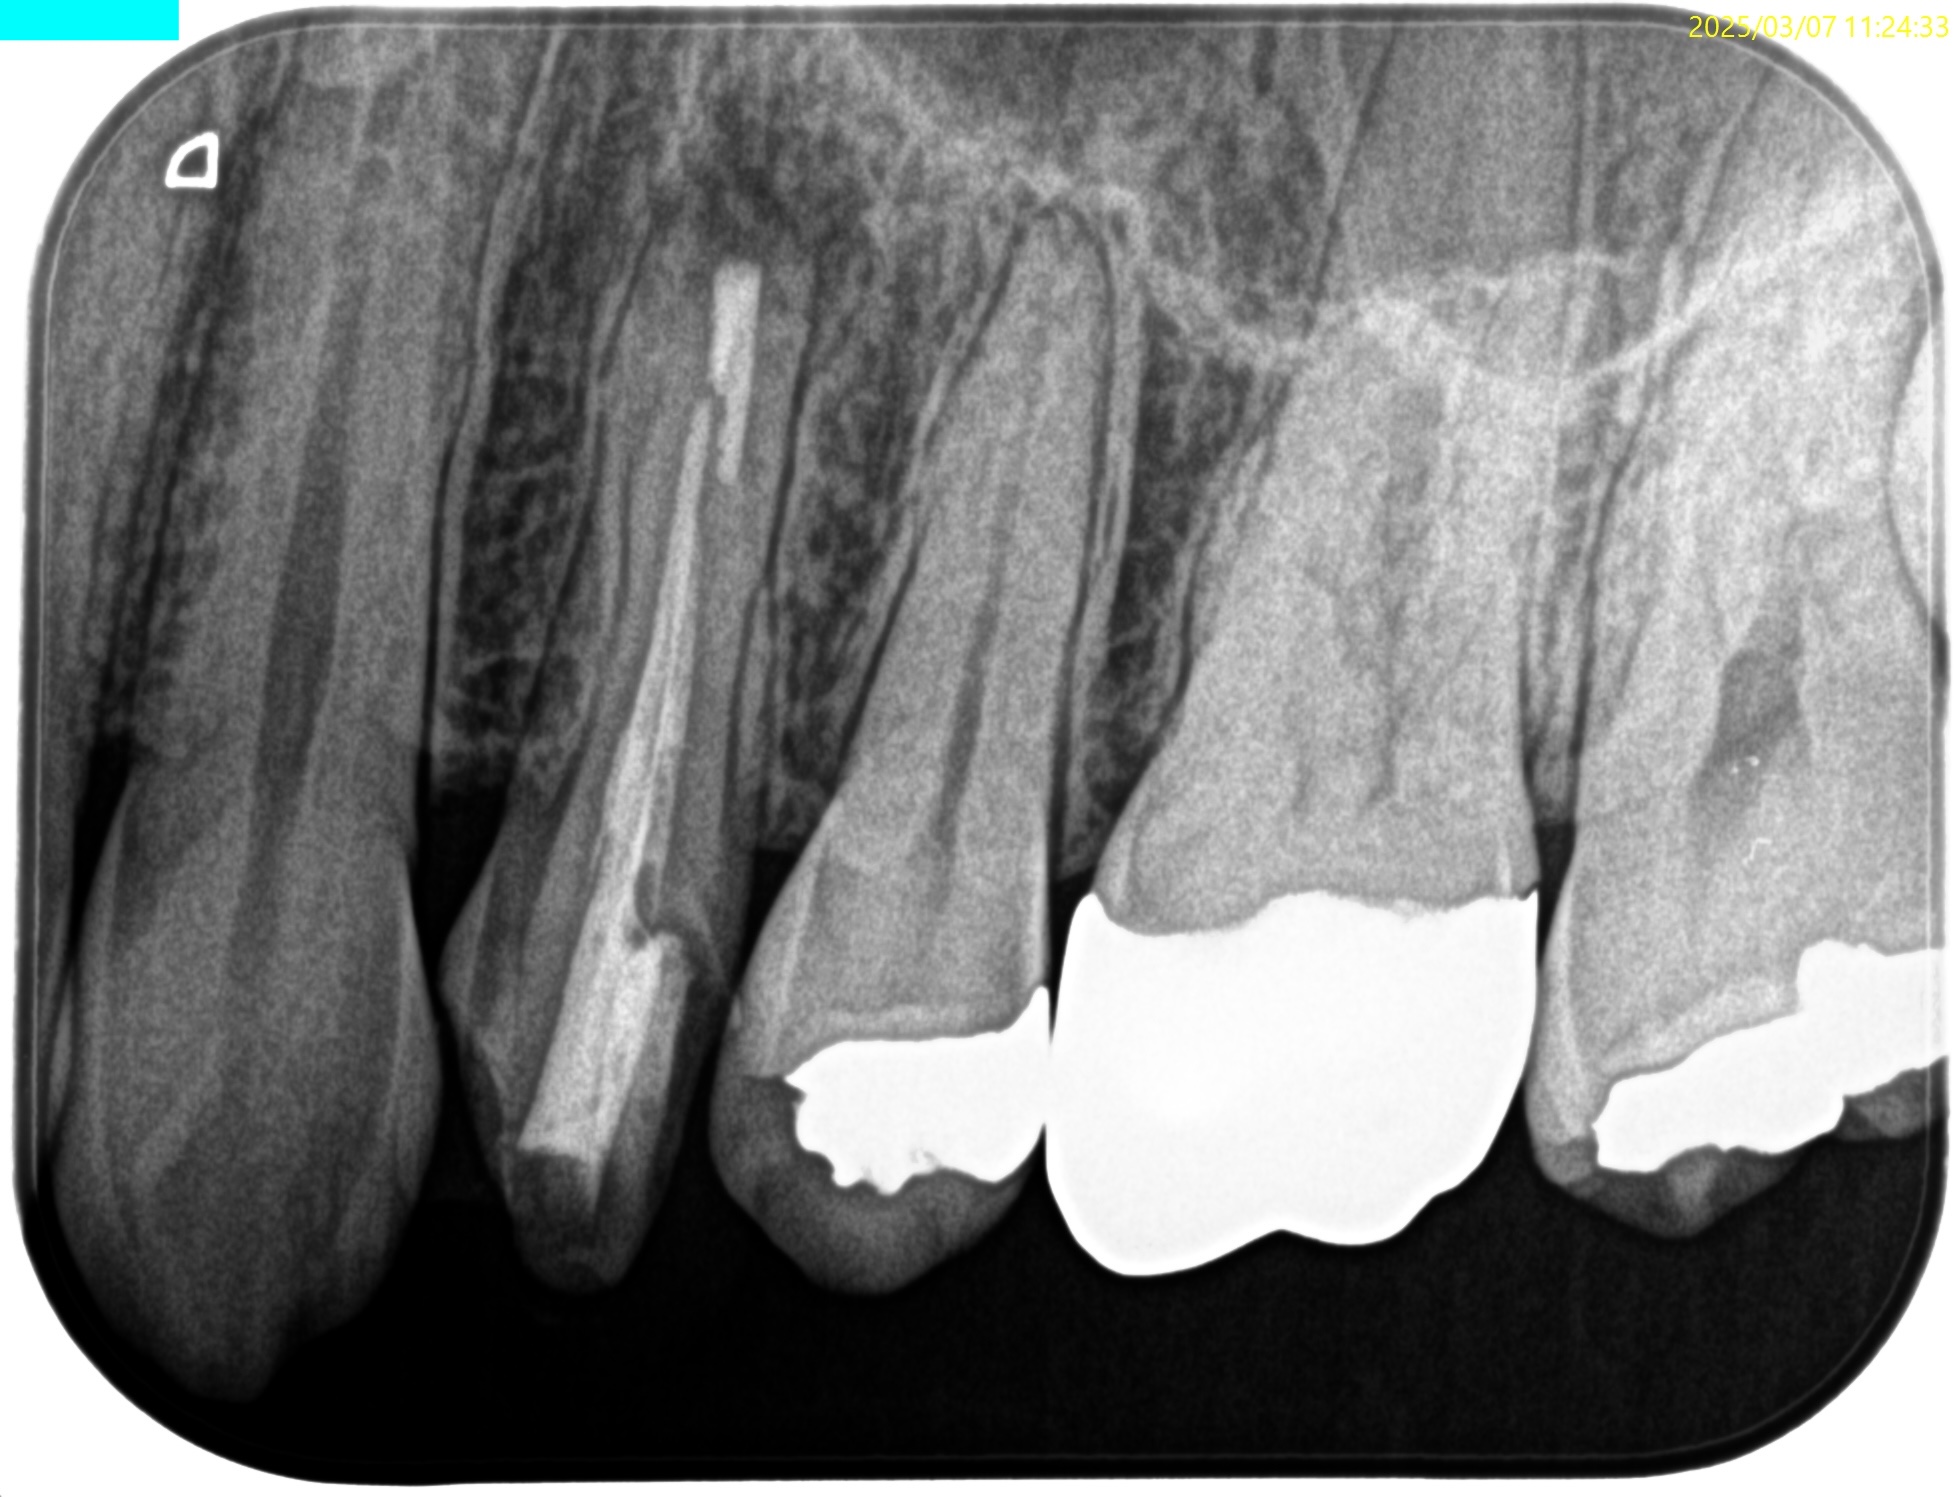

#12 RCT(2024.3.7)

ここから1年が経過した。

#12 RCT 1yr recall(2025.1.7)

根管治療が奏功しなかった。

では、再根管治療か?といえば、初期治療で穿通できなかったのである。

ということは、治療方法はApicoectomy一択だ。